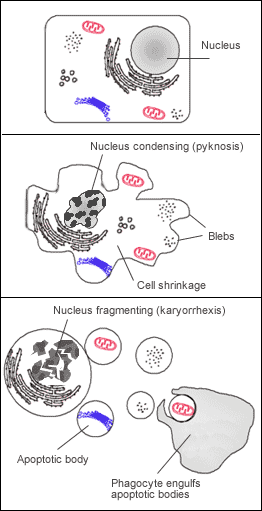

Many pathways and signals lead to apoptosis, but these converge on a single mechanism that actually causes the death of the cell. After a cell receives stimulus, it undergoes organized degradation of cellular organelles by activated proteolytic caspases. In addition to the destruction of cellular organelles, mRNA is rapidly and globally degraded by a mechanism that is not yet fully characterized.[42] mRNA decay is triggered very early in apoptosis. A cell undergoing apoptosis shows a characteristic morphology:

- Cell shrinkage and rounding are shown because of the breakdown of the proteinaceous cytoskeleton by caspases.[43]

- The cytoplasm appears dense, and the organelles appear tightly packed.

- Chromatin undergoes condensation into compact patches against the nuclear envelope (also known as the perinuclear envelope) in a process known as pyknosis, a hallmark of apoptosis.[44][45]

- The nuclear envelope becomes discontinuous and the DNA inside it is fragmented in a process referred to as karyorrhexis. The nucleus breaks into several discrete chromatin bodies or nucleosomal units due to the degradation of DNA.[46]

- The cell membrane shows irregular buds known as blebs.

- The cell breaks apart into multiple vesicles called apoptotic bodies, which are then phagocytosed.